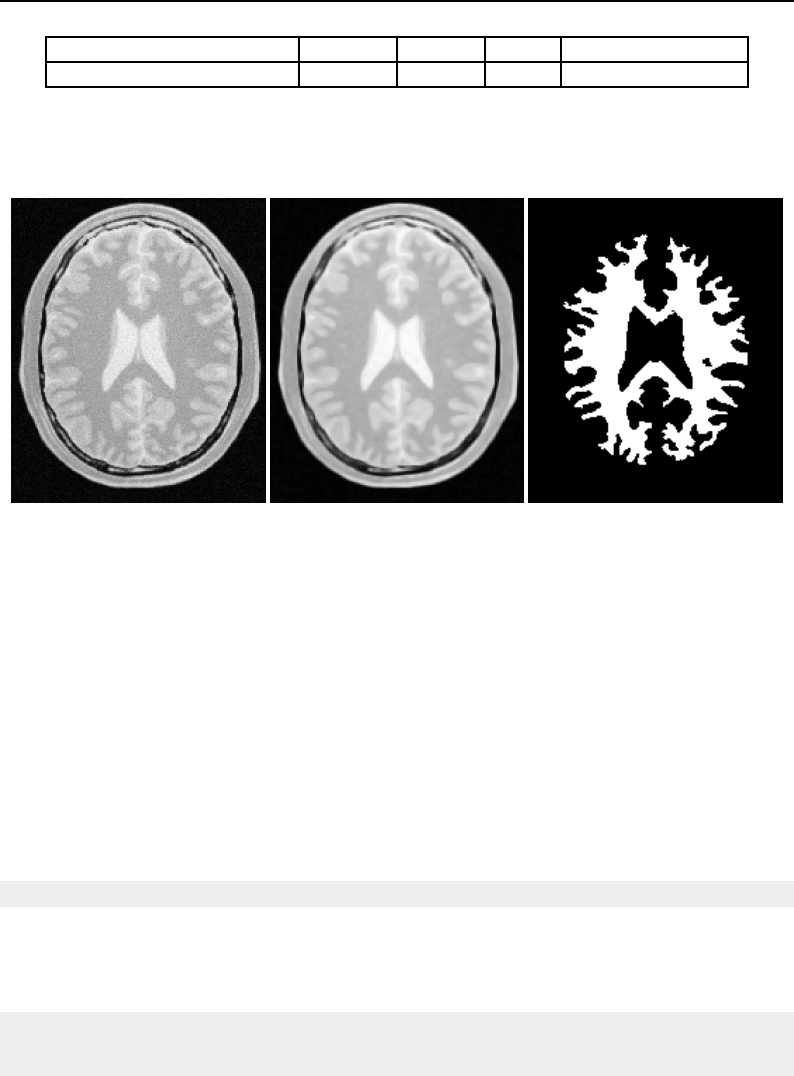

The National Library of Medicine Insight Segmentation and Registration Toolkit, shortened as the

Insight Toolkit (ITK), is an open-source software toolkit for performing registration and segmenta-

tion. Segmentation is the process of identifying and classifying data found in a digitally sampled

representation. Typically the sampled representation is an image acquired from such medical instru-

mentation as CT or MRI scanners. Registration is the task of aligning or developing correspondences

between data. For example, in the medical environment, a CT scan may be aligned with a MRI scan

in order to combine the information contained in both.